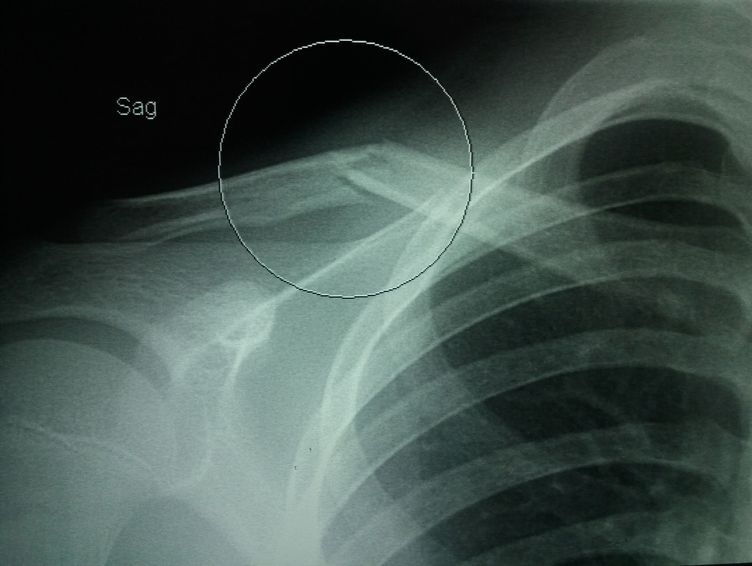

Clavicle

Mid shaft clavicular fracture?